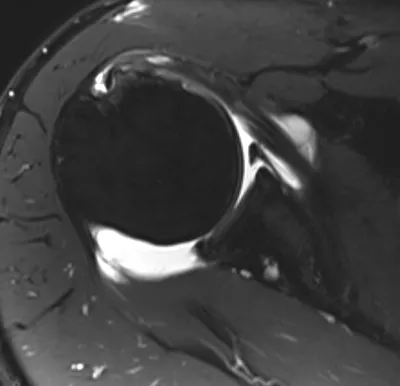

SLAP tear

Arthrogram

4/11/2026